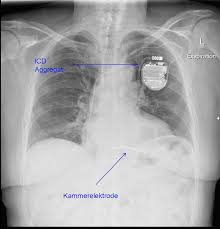

Herzrhythmusstorungen Komplett Subkutaner Icd Erfullt Die Anforderungen Springermedizin De

Herzrhythmusstorungen Komplett Subkutaner Icd Erfullt Die Anforderungen Springermedizin De from media.springernature.com